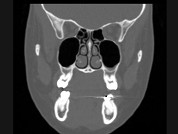

- 多项选择题女,25岁, 车祸伤及面部,X线及CT检查如图所示, 正确的描述或诊断是 ( )

A、X线示左侧眶底较正常变低

B、CT发现左侧眶底骨质断裂

C、左侧上颌窦内见气-液面

D、左侧眶底骨折

E、左侧上颌窦积液